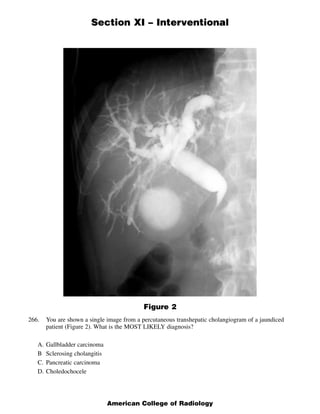

This document contains 5 clinical case scenarios involving interventional radiology procedures (questions 265-269). Each case is accompanied by an image and 4 possible answers. The correct answer is identified and a brief rationale is provided for each case. Question 270-279 continue testing knowledge of interventional radiology with additional multiple choice questions related to procedures, techniques, and disease processes.